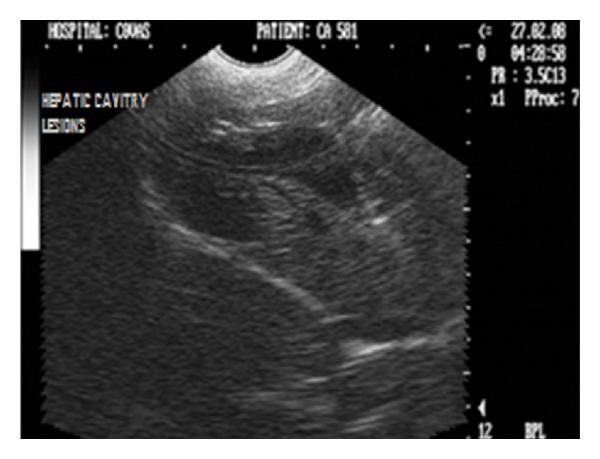

Hepatic disease is often treatable and has a predictable prognosis when a definitive diagnosis is made. The aim of clinicopathological evaluation of hepatobiliary affections is to identify and characterize hepatic damage and dysfunction, identify possible primary causes of secondary liver disease, differentiate causes of icterus, evaluate potential anaesthetic risks, assess prognosis and response to xenobiotics, and monitor response to therapy. This paper describes the different diagnostic methods and imaging techniques employed in diagnosis of hepatobiliary affections in dogs. Besides reviewing the significant clinical manifestations and imaging structural abnormalities in diagnostic approach to different hepatic affections, it also depicts radiographic, ultrasonographic, and wherever applicable, the laparoscopic characterization of different hepatic affections and target lesions encountered in clinical cases presented in the Teaching Veterinary Clinical Complex, COVAS, Palampur in the year 2007-2008.

肝病通常是可治疗的,一旦做出明确诊断,其预后是可预测的。肝胆疾病临床病理评估的目的是识别和描述肝损伤及功能障碍,确定继发性肝病可能的主要病因,鉴别黄疸的病因,评估潜在的麻醉风险,评估预后及对外源化学物质的反应,并监测治疗反应。本文描述了用于诊断犬肝胆疾病的不同诊断方法和成像技术。除了回顾不同肝病诊断方法中的重要临床表现和成像结构异常外,还描述了2007 - 2008年在帕兰普尔兽医临床综合教学中心(COVAS)出现的临床病例中不同肝病及目标病变的放射学、超声学特征,以及在适用情况下的腹腔镜特征。